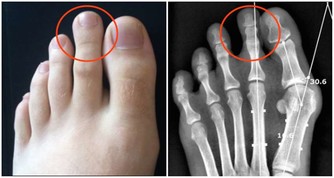

8. 非抗炎解熱鎮痛藥減緩背痛。

許多人會使用非抗炎解熱鎮痛藥來治療背部疼痛或關節炎,但這些藥物的效果其實非常有限,更重要的是,使用過多的話還可能導致肝臟出現問題。事實上,非類固醇消炎藥對於治療背痛還比較有效,但這種藥會有嚴重的副作用,也是無法長期服用。專家建議最有效的改善方法還是增強肌肉強度,但這需要時間。